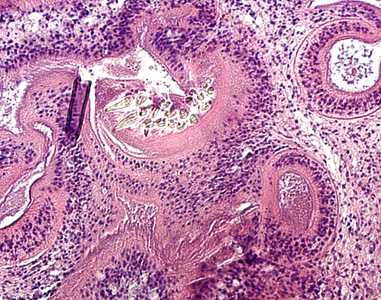

Coenuri in tissue specimens, stained with hematoxylin and eosin (H&E).

Figure A

Figure A: Coenurus removed from a subcutaneous nodule in the shoulder area of a patient, stained with hematoxylin and eosin (H&E). Image taken at 50x magnification. Although the species was not identified in this case, the pathology is consistent with T. serialis.

Figure B: Higher magnification (200x) of the coenurus in Figure A.